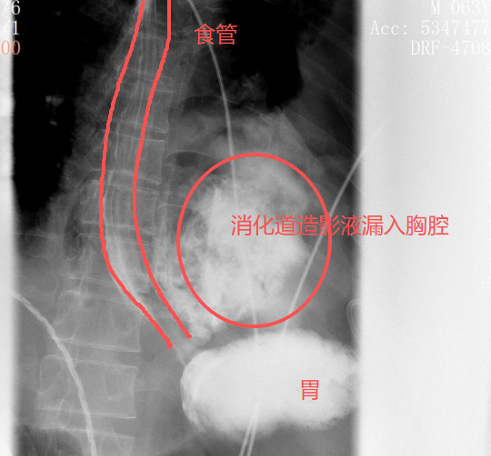

老伴吓得赶紧拨打了120。当晚7点多,他被紧急送到就近医院。胸片结果很快显示:左侧胸腔大量积液。止痛针打了,积液引流做了,但疼痛丝毫没有止住。更糟糕的是,张叔的状态越来越不稳定,眼看就要陷入休克。

凌晨2点,他被紧急转送到北京大学深圳医院。此时,他还不知道,自己的食道,已经在剧烈的呕吐中裂开了一道长达10公分的口子,胃里的食物和胃酸,正源源不断地漏进胸腔里。